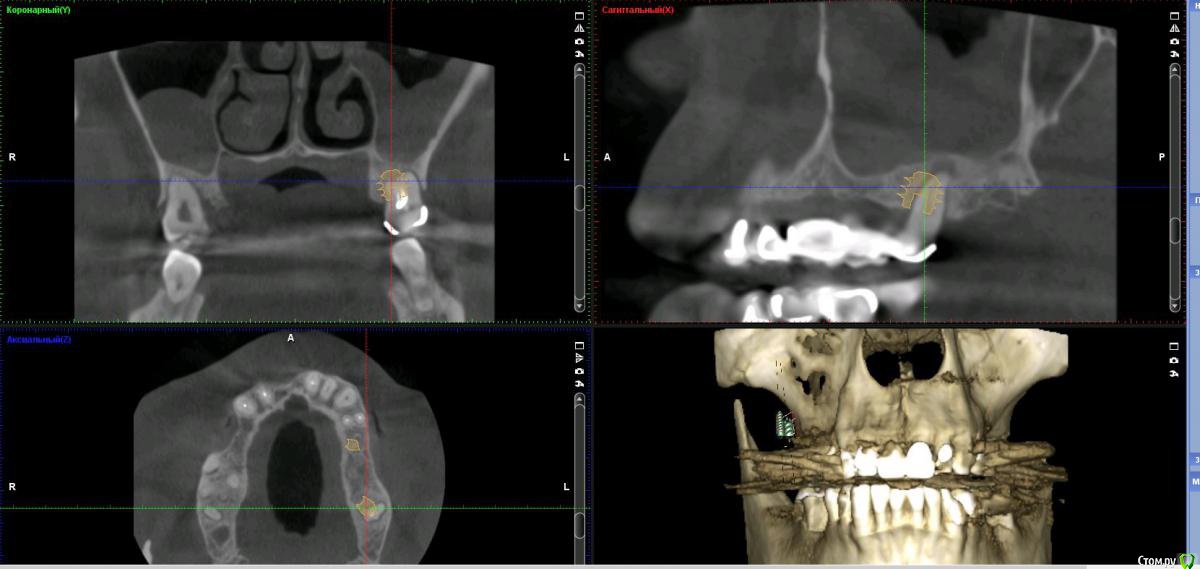

Дмитрий Л. Опубликовано 16 ноября, 2018 Поделиться Опубликовано 16 ноября, 2018 (изменено) Здравствуйте всем)Ситуация такая: старый мост 24-28. 28 симптоматичен, пациент принимает аб и противовосп. Имеется: - 24 перирадикулярные изменения (асимптомно)- 28 перирадикулярные изменения (обострение)- утолщение слизистой гайморовой (асимптомно)- невозможность имплантации в обл 26 (высота кости не позволяет) Пожелания пациента:- удаление 28 - желание сохранить мост - имплантация - нежелание носить съемную конструкцию Как планирую я:- перелечить 24, кальций 2-6 мес.- удалить 28- изготовить съёмник- выждать 4-6 мес. Повторить КТ, оценить гайморовую- имплантация 25, имплантация "где-то в обл 27" - всеми силами избежать синуса Мои грёзы:1. Ставить вблизи 24 - риск. Нужно лечить 24... реэндо... долго... может удалить? 2. Я верю, что причина хр гайморита - 28. Так ли это? Стоит ли ожидать позитивной динамики? 3. На сколько уйдёт кость после удаления 28 за 4-6 мес.? Её и так мало... Станет ли меньше? Графтить 28 не хочу. Там микробы. 4. Объём кости в обл 27-28 требует коротышку. Первыми приходят на ум Штрауман 6 мм (4 мм в кости, станет красиво) или ЭниРидж (бикортакально, скорее всего в пазуху на 1-2 мм). Нюанс в том, что я не работал этими системами... И коротышки не ставил. В общем придётся искать наборы, но это мои проблемы. 5. Итоговая конструкция: мост 25-27. При чём 27 имеет длину 4-6 мм, не слишком ли короткая дистальная опора? Вот спланировал приблизительно так... Надеюсь на отклик. Изменено 16 ноября, 2018 пользователем Дмитрий Л. Ссылка на комментарий

Neilrus Опубликовано 16 ноября, 2018 Поделиться Опубликовано 16 ноября, 2018 У эниридж есть совсем коротыши 5,5х5, для семерки, если не хотите лезть в синус самое то, у него огромная площадь получается за счет особенностей резьбы. Только для него набор специальный с ограничителями должен быть, но дилер может и даст в аренду за имплантат, покупать его не вижу смысла, нужен раз в полгода 1 Ссылка на комментарий